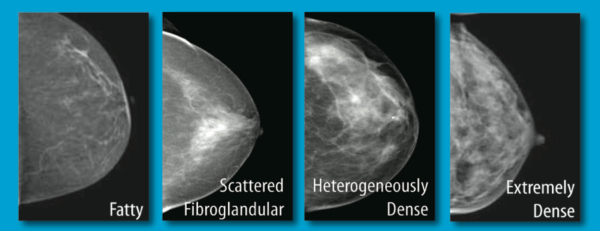

Breast Tissue Density awareness